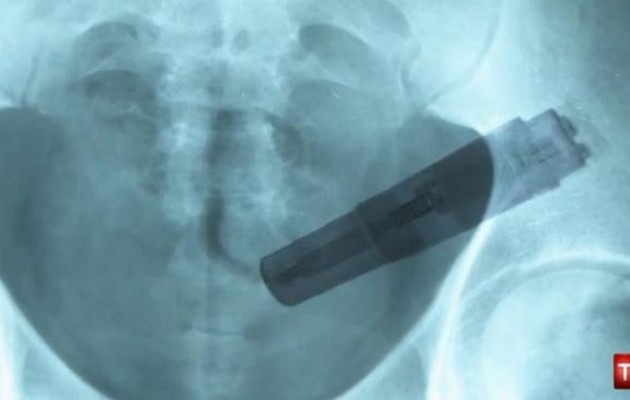

Η γνωμάτευση του ιατροδικαστή στο Σάουθαρκ στην Βρετανία ήταν σοκαριστική αλλά δεν σήκωνε και καμία αμφισβήτηση.

Ο 50χρονος Νάιτζελ Γουίλις πέθανε εξαιτίας του δονητή που είχε σφηνώσει μέσα του για 5 ημέρες.

Ο Νάιγκελ Γουίλις ζούσε με την ηλικιωμένη μητέρα του και οδηγήθηκε εσπευσμένα στο νοσοκομείο, στις 30 Δεκεμβρίου του 2013, με τον δονητή στον πρωκτό του.

Οι γιατροί που τον εξέτασαν κατάφεραν να βγάλουν τον δονητή από το σώμα του αλλά δυστυχώς μετά από 2 μήνες πέθανε από τις επιπλοκές στην υγεία του που είχε προκαλέσει το ατύχημα.